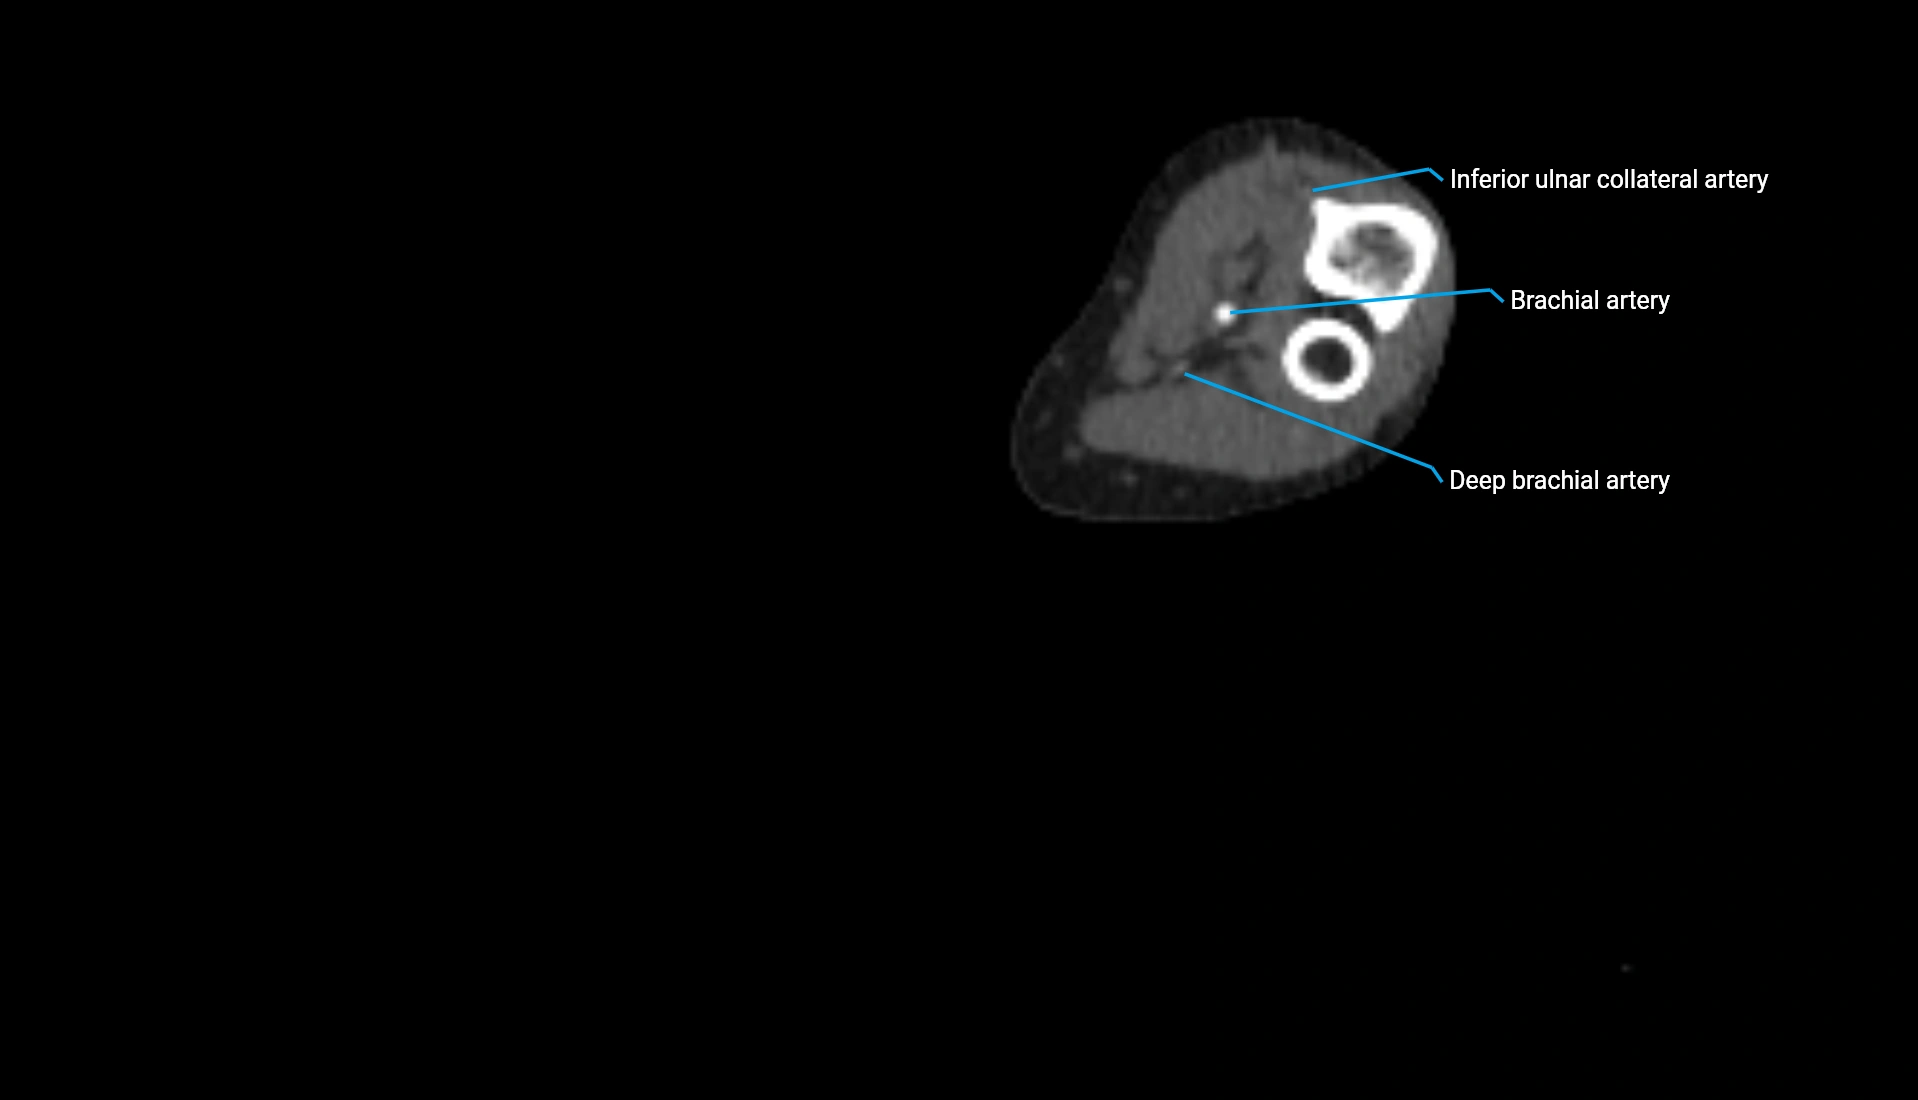

CT Appearance

Non-Contrast CT:

• Cortex: High-density, sharply defined

• Subchondral bone: Dense cancellous matrix

• Articular surface: Smooth concave contour articulating with the capitellum

• Excellent for evaluating bone integrity, alignment, and subtle fractures

Post-Contrast CT:

• Bone: No enhancement

• Joint capsule and synovium: Mild enhancement outlining the joint

• Improves contrast between soft tissues and bony margins

• Useful in detecting subtle joint abnormalities or postoperative changes